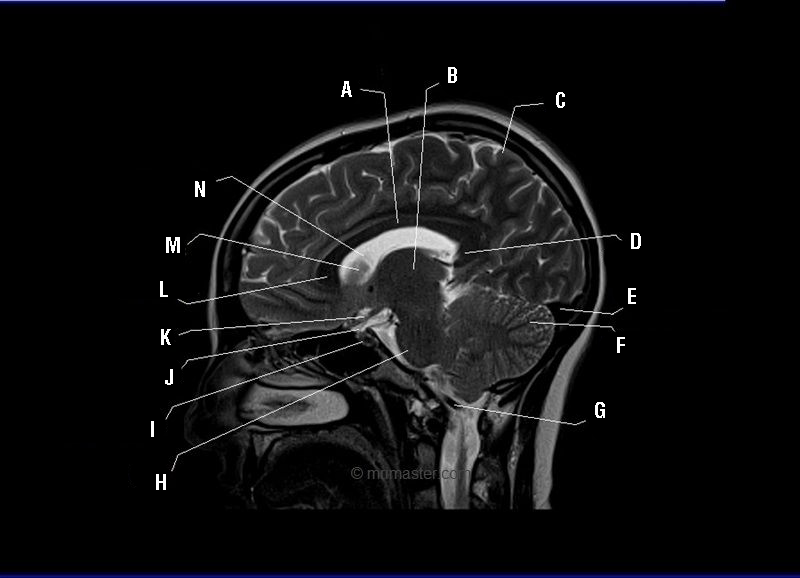

What is A?

Body of corpus collosum

What is B?

Thalamus

What is C?

Grey matter

What is D?

Splenium of corpus collosum

What is E?

Transverse sinus

What is F?

Cerebellum

What is G?

Vertebral artery

What is H?

Pons

What is I?

Pituitary gland

What is J?

Pituitary stalk

What is K?

Optic chiasm